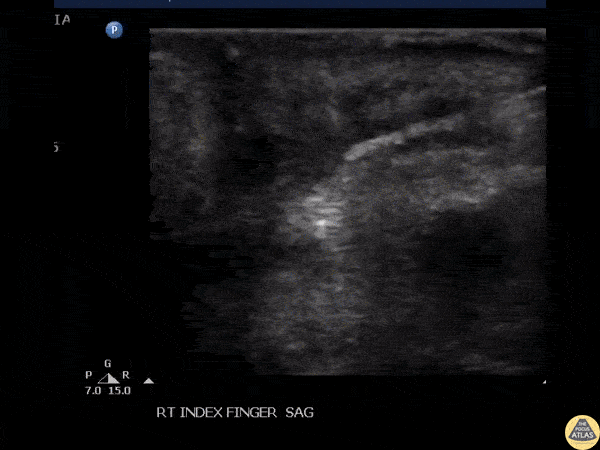

Soft Tissue - Foreign Body Removal

Ultrasound guided removal of a wooden foreign body. Image courtesy of Robert Jones DO, FACEP @RJonesSonoEM Director, Emergency Ultrasound; MetroHealth Medical Center; Professor, Case Western Reserve Medical School, Cleveland, OH View his original post here